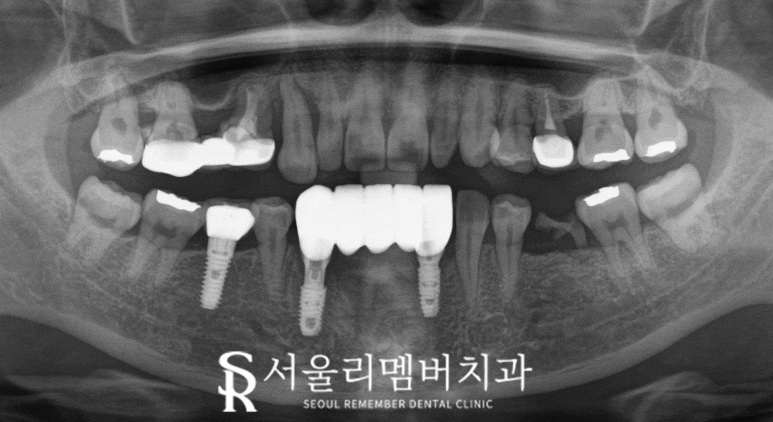

발치 후 내비개이션 임플란트 를 통해

식립 위치를 미리 설정해서 그대로

정확하게 식립할 수 있었습니다.

이 과정에서 치조골의 많은 흡수로

임플란트를 지지해 줄 뼈가 없었기에

뼈 이식을 동반하여 더욱 신중하고

안전하게 심는 것이 중요했습니다.

또한 해당 부위가 앞니였기 때문에

회복 후에도 만족할 수 있도록

미관까지 고려하여 보철물을 제작했습니다.

진료 종료 후 이제 안정적으로 저작 기능을 회복하시고,

흔들림 없는 치아를 다시 찾게 되셨습니다.

더 확실한 차이를 보여드리기 위해

전 후 사진을 비교해 봤는데요,